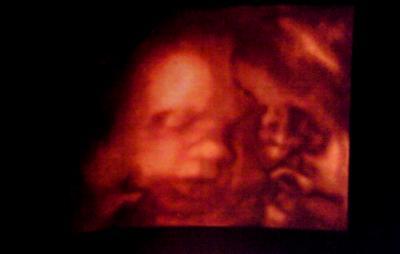

Hatte heute wieder einen Termin beim FA Der kleine wiegt jetzt 1500 gramm, laut US hätte ich den ET am 16 März (eigentlich der 29 März) mal gucken wann er kommt. Hatte vielleicht grade einen wachstumsschub und laut der Waage beim FA habe ich 8,5 Kilo zugenommen Musste sehr lange warten und ich lag 30 min am CTG, mein Mann war schon ganz nervös und genervt. Sind eure da auch so? Ich glaube er kommt nicht mehr oft mit^^, er erkennt eh NIE etwas auf dem Ultraschall. Auch wenn der FA alles erklärt. Und das schönste ich habe Bilder bekommen, schicke sie gleich mal mit. Könnte meinen kleinen ja den ganzen Tag auf dem US betrachten. Er hatte kurz seine halbe Hand im Mund, und dann gähnte er. Bin so happy gerade. Morgen kommen die Kartons mit den Babysachen vom Dachboden und ich habe GV. Sooooo schön alles.... @scarlett der nächste Termin ist der 19 Januar. Umarme euch alle zusammen ganz fest

Bild Nr 2 mit zerknautschtem Gesicht